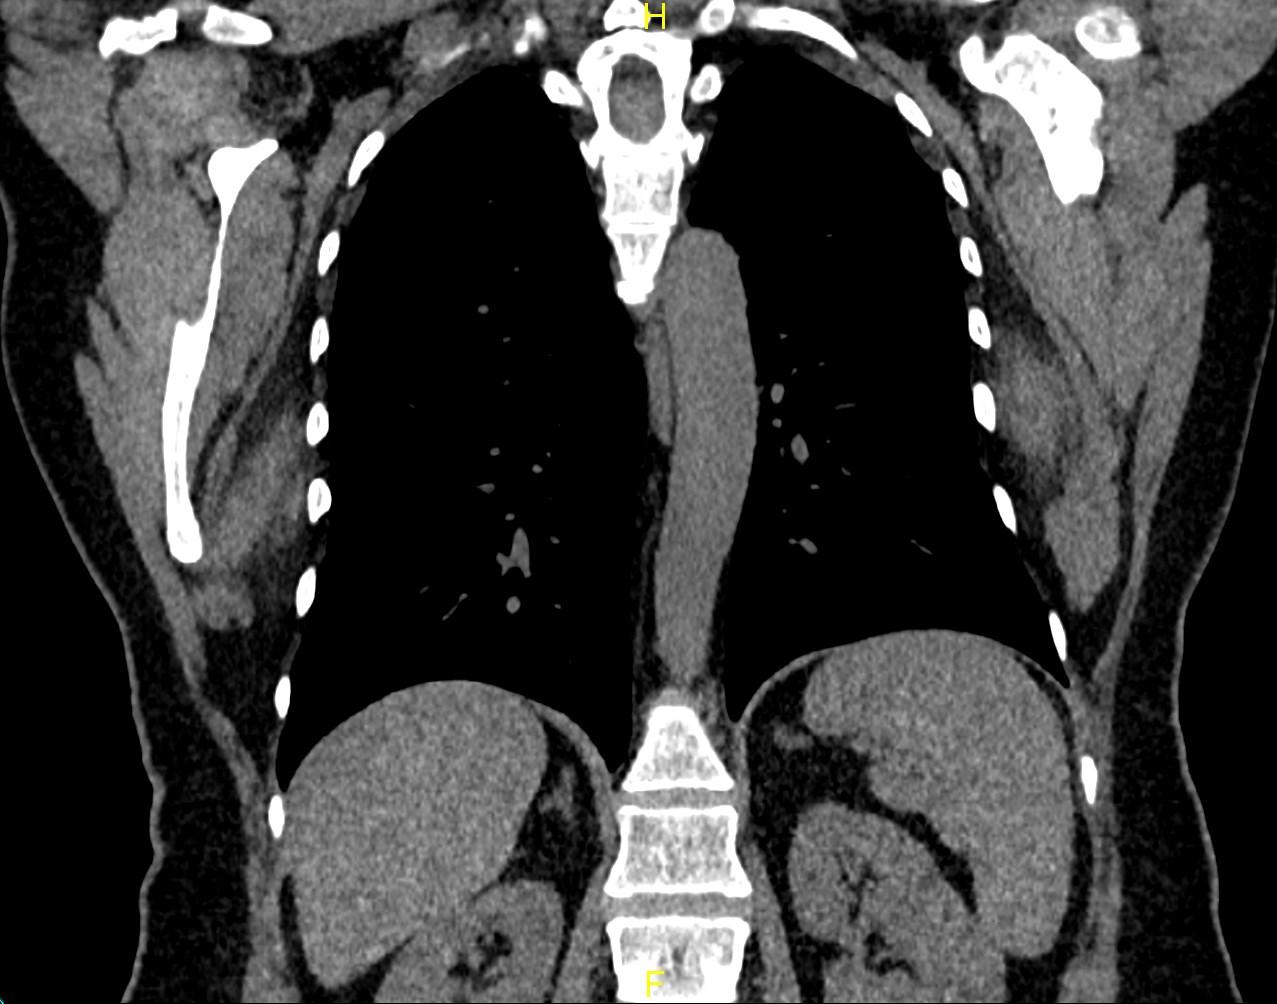

CT images showed bilateral poorly defined soft-tissue mass with attenuation similar to that of the adjacent skeletal muscle. They are located in the infrascapular region suggestive of elastofibroma dorsi lesions.

Elastofibroma dorsi is a benign soft-tissue tumor with a characteristic location and imaging appearance.

Elastofibroma dorsi is more frequently seen in older women. The estimated mean age at diagnosis is around 65-70 years.